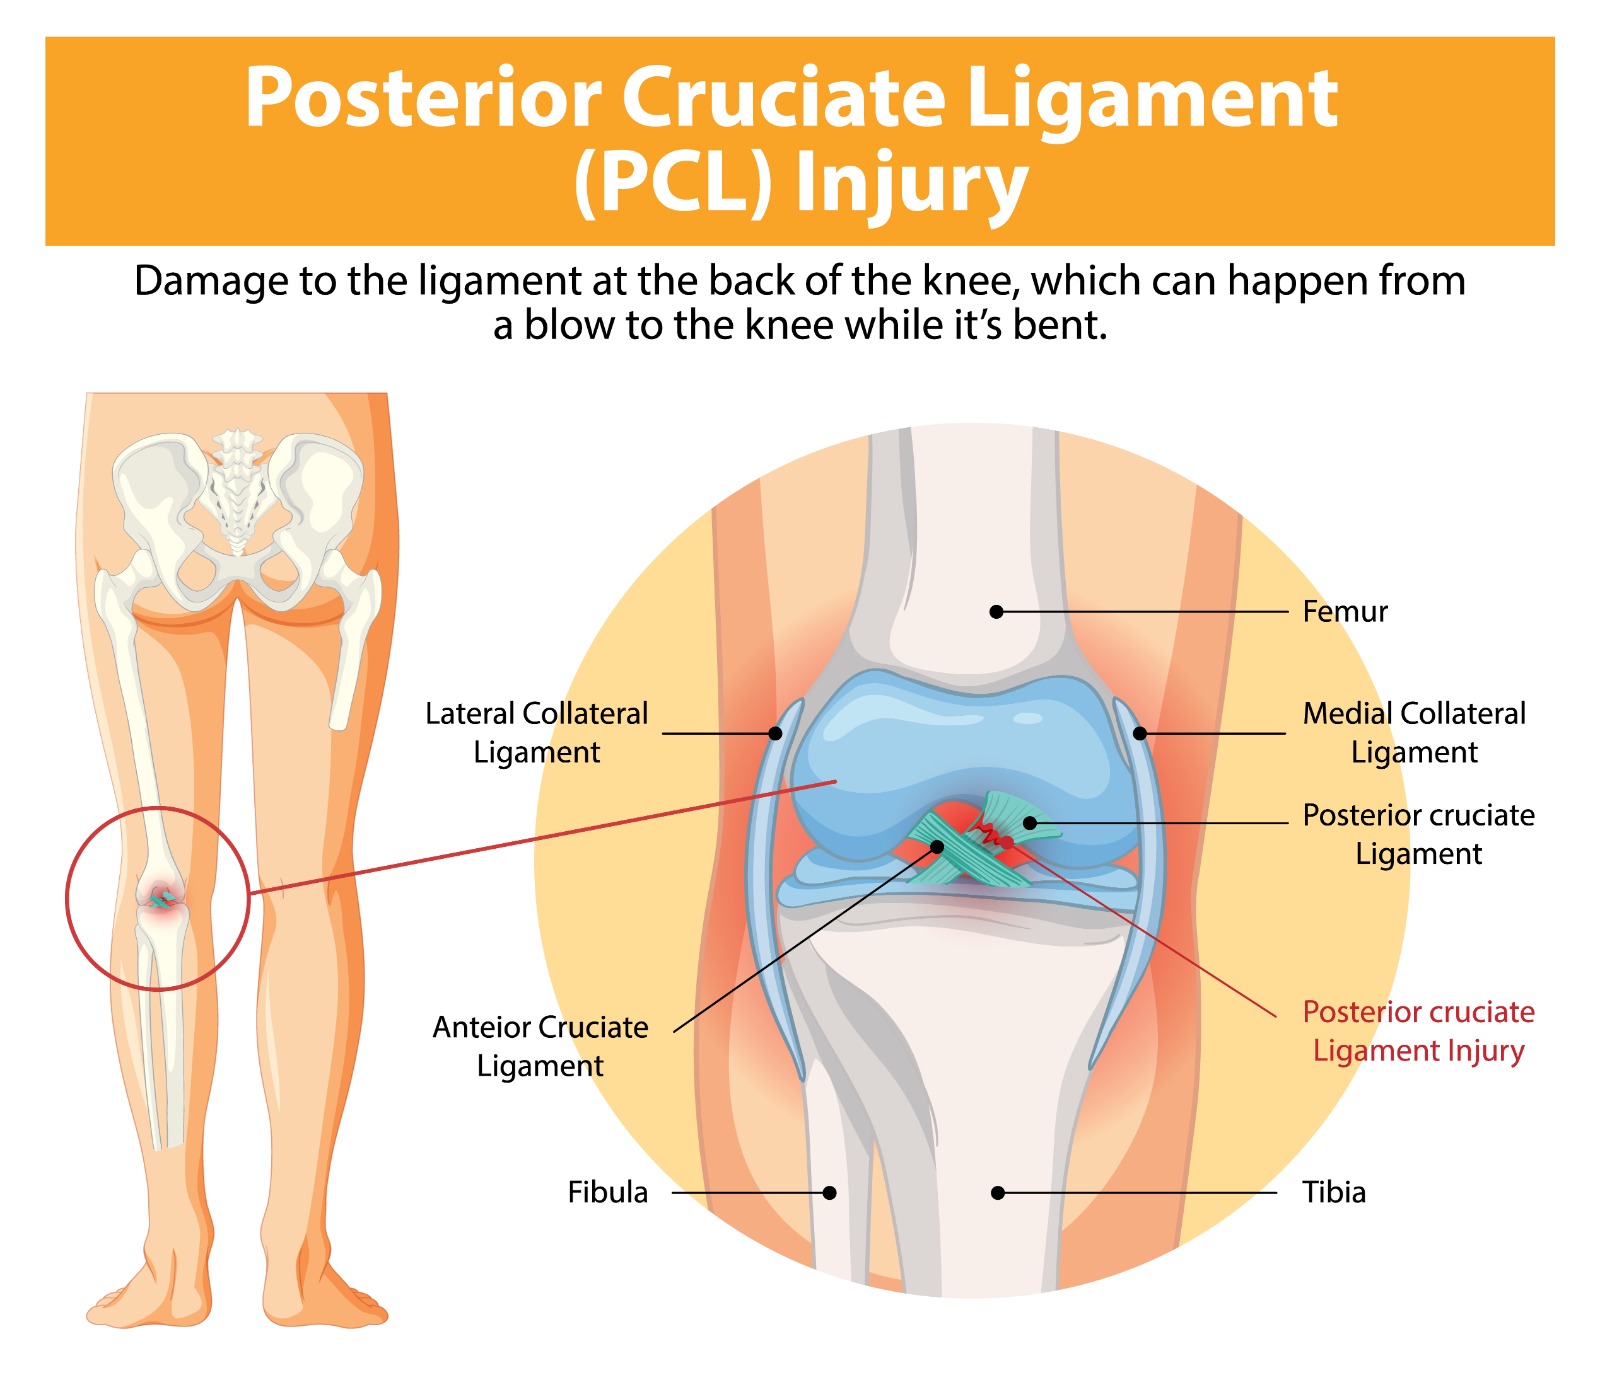

The posterior cruciate ligament (PCL) is the strongest ligament in the knee, preventing the tibia from sliding backwards relative to the femur. PCL injuries, though less common than ACL tears, account for a significant proportion of serious knee ligament injuries — particularly in contact sports, road traffic accidents, and high-energy trauma. They range from isolated grade I sprains to complete grade III ruptures, often occurring alongside injuries to other knee ligaments in complex multi-ligament knee injuries.

- Direct blow to the front of the bent knee — the ‘dashboard injury’ in road traffic accidents

The posterior drawer test and posterior sag sign are the key clinical tests. Stress X-rays quantify the degree of posterior tibial translation. MRI confirms PCL injury and identifies associated ligament, meniscal, and chondral pathology. CT angiography may be required if knee dislocation is suspected.